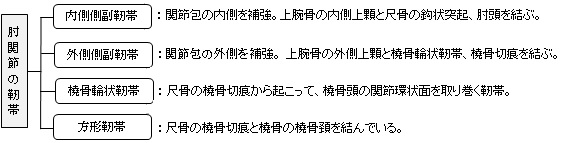

以下が肘関節を補強する靭帯になる。

In the latter case, the ligaments are collectively referred to as the lateral collateral ligament complex (LCLC), consisting of four ligaments:[1]

- the radial collateral ligament [proper] (RCL), from the lateral epicondyle to the annular ligament deep to the common extensor tendon[1]

- the lateral ulnar collateral ligament (LUCL), from the lateral epicondyle to the supinator crest on the ulna. Near the attachment on the humerus this ligament is normally indistinguishable from the RCL and can be considered the posterior portion of it.[1] Martin 1958 described the distal part of the LUCL as "a definite bundle which normally crosses the annular band and gains attachment to the supinator crest, frequently to a special tubercle on that crest" but didn't name it.[3]

- the annular ligament (AL), from the posterior to the anterior margins of radial notch on the ulna, encircles the head of radius

- the accessory lateral collateral ligament (ALCL). from the inferior margin of the annular ligament to the supinator crest」